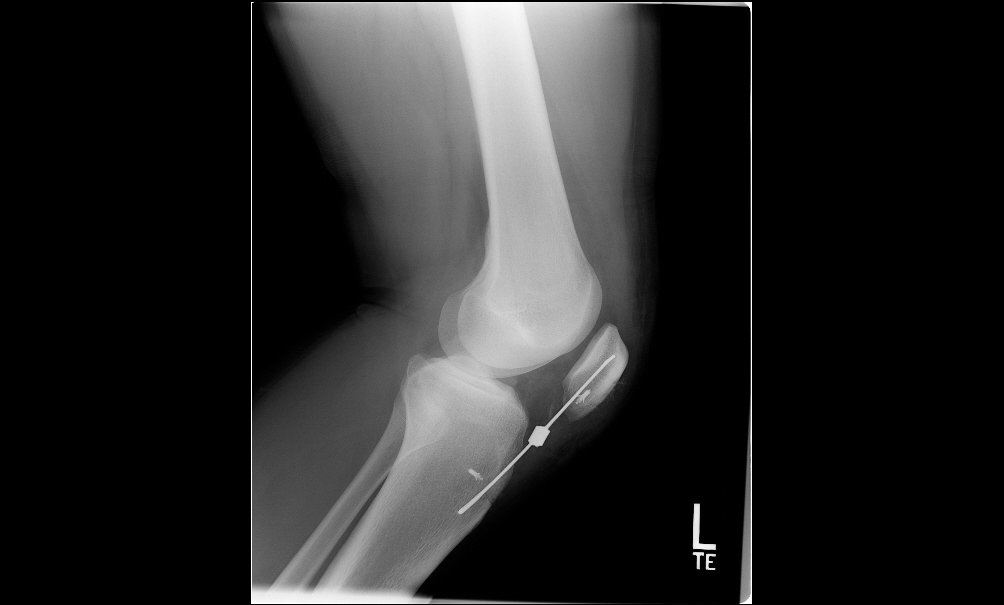

Knee Fractures